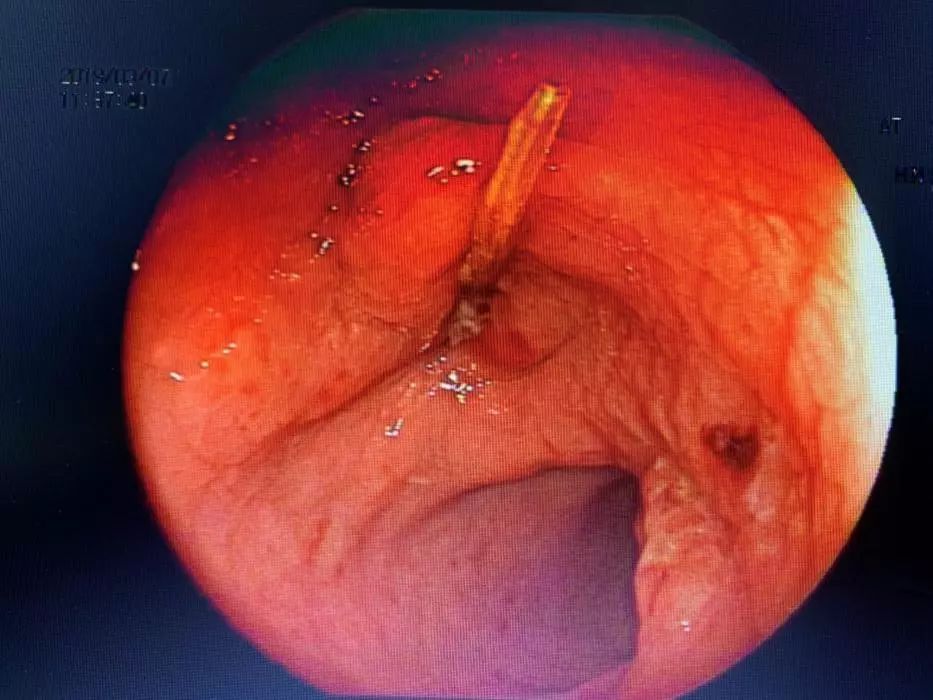

随后在CT和肠镜中,医生们惊奇地发现,李先生的盆腔里,有一个神秘的条!状!物!

它一头扎在肠内,另一头在肠外。

▲ 内镜下看到的杆状物